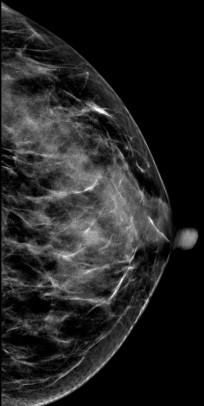

2D图像:

常规2D图像在MLO位上象限发现靠近胸大肌处见一不对称团块影,CC位上并没有发现明显肿块影,右乳外象限局部结构较乱,DBT图像左乳外上象限清晰可见一不规则肿块影,呈分叶状,与周边腺体组织界限欠清

影像诊断:

左乳外上肿物--考虑良性可能性大BI-RADS 3级